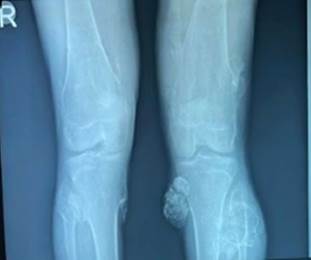

The

patient had undergone radiological examination and X-ray knee showed multiple

pedunculated exostosis noted on either side of distal end of femur, Proximal

end of tibia and fibula

(Figure 1).

Figure

1.

Xray image of the patient showing lobulated mass over tibia and fibula.